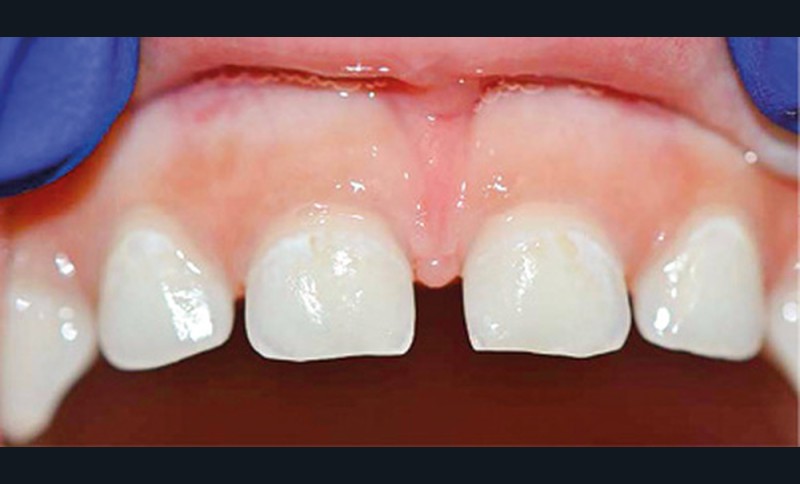

- L’évolution de la maladie carieuse : cette pathologie bactérienne, multifactorielle, se transmet très vite d’une dent à une autre dans la cavité orale de l’enfant. Ainsi, avant l’âge de 6 ans, la carie précoce de l’enfant (CPE) peut atteindre un stade sévère et ne plus permettre à l’enfant de mastiquer sans douleur (fig. 2).

- La perte de chance pour le développement : la CPE non traitée va entraîner l’avulsion précoce de certaines dents, induisant des troubles alimentaires pouvant se répercuter sur le développement général de l’enfant (croissance et développement cognitif), voire de sa vie sociale (absences scolaires répétées, pas de sourire). La CPE a un impact négatif sur la qualité de vie de l’enfant.